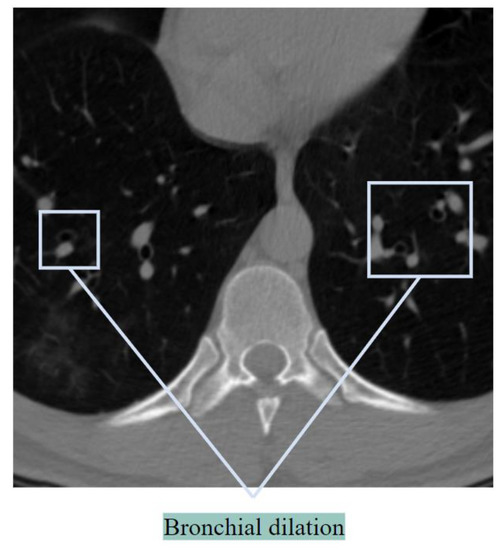

Bronchial Dilatation

In healthy lungs, the diameter of a bronchus is either equal to or slightly smaller than the diameter of its neighboring artery. When the bronchus is considerably larger than the size of the accompanying artery, this is called bronchial dilation, and BA pairs can look like a signet ring [17]. Figure 3 illustrates the bronchial dilation.

Figure 3. Bronchial dilation showed in a CT scan.

If Figure 3 is carefully observed, it can be seen that the BA ratio (ratio of the diameter of the bronchus to its accompanying artery) is increased, and the BA pair can be perceived as a signet ring sign. The challenge is the detection of discrete BA pairs having a signet ring shape. In many cases, a bronchus is close to multiple arteries, or several bronchi may appear together, which complicates the matter. Bronchial dilation has also been detected in some COVID-19 cases, with a BA ratio that was almost doubled [10]. In the case of pneumonia, dilatations occur along with the destruction of bronchi.